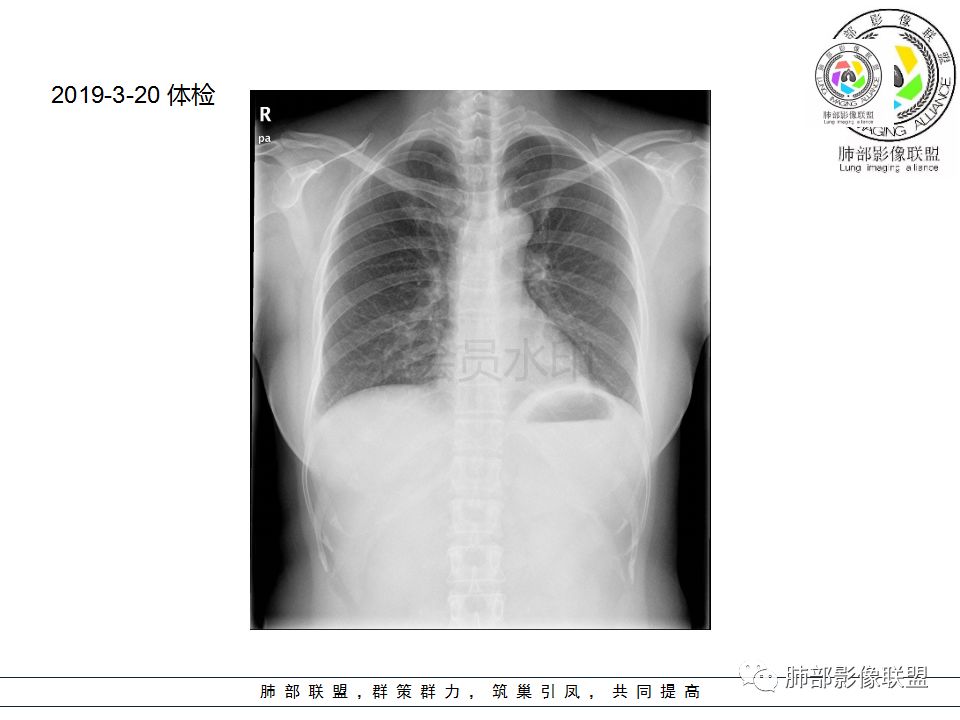

【每日晨读】看似正常的胸片---原是蛰伏不露!

看似繁花似锦,也会暗流涌动。一张普通的胸片在基层很常见了,在一张看似正常的胸片后面隐藏了什么?敬请各位来分析。

Shelia:侧位心后间隙变小,下肺野与心影重叠区怀疑有斑片影

正位实在看不出什么问题

Coke with ice:唉……我都没找出来病变在哪……平片的老师们指点指点南边:

看完第二部分大家再说说看有什么体会?宇宙星空:左侧膈面上片状高密度影

M-Imaging :盘状不张不是,盘状不张,胖人腹压高多见远方:如南大所标示,标准答案。正位提示左肺下野与膈面重叠密度增高影,边缘光滑,侧位可再定位具体一点后肋膈角区密度增高影,具体是肺内肺外都有可能,盘状肺不张、肺内肿块、肺外病变(胸膜来源和膈肌来源)等都可以。我的体会常规正片再加负片结合这个肯定不会漏的,负片很有价值,平片发现问题就好,具体我们还是进一步CT检查了。

远方:基层医院很多都是X线为主,胸片占了一半以上,专科除外,正侧位片往往不重视侧位,临床医生也经常未要求侧位,考验我们影像医生了。这个单凭正位往往就漏了。恰好病变上缘与膈肌面比较重合。

Shelia:尤其体检基本不照侧位片Coke with ice:嗯,很有警示意义的病例。我倾向于定位胸膜来源,SFT?